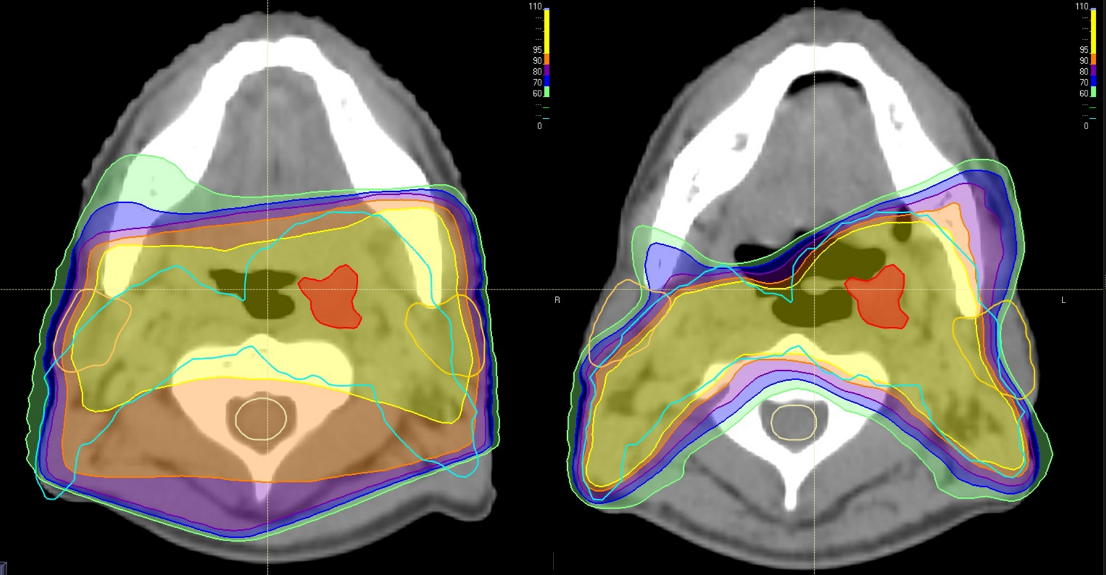

以下に実際に放射線の当たる部位をお示しします。

黄色や橙色など暖色部分は放射線が強めに当たる範囲です。色が付いていない部分は放射線がほとんど当たっていないことを示しています。このようにI M R Tを用いて放射線治療を行うことで、正常臓器の放射線量を下げながら病巣へ集中した治療を行うことができます。